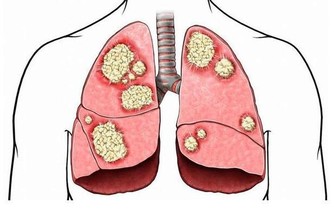

痔瘡症狀嚴重,通過改善以上家庭療法還無法消除症狀時,也可以考慮膠圈套紮法,即在痔瘡根部套入小型膠圈,痔瘡逐漸缺血、壞死。紅外線光凝、冷凍等,都是通過冷熱刺激,直接使痔瘡壞死。

當症狀嚴重,出現痔核嵌頓等嚴重影響到正常生活的症狀時,就要考慮對痔瘡進行手術切除了。